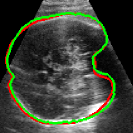

As mentioned in Sec. 3.2, it is crucial for our brain extraction network to work consistently regardless of the orientation of the brain within the US volume. This can be qualitatively observed in Fig. 3, which shows the outline of the brain-extraction prediction and the corresponding ground-truth, in red and green respectively, for six different 3D US volumes. These volumes have been selected to demonstrate the amount of variation between each scan, with the position of the fetus inside the mother as well as the position of the brain in respect to the scan varying drastically from case to case.

As shown in Fig. 3 , the network’s prediction is remarkably close to the ground-truth, regardless of the position of the brain in the volume. It also manages to accurately predict the location of the brain when this is partially obscured either by the cropping or the shape of the ultrasound beam.

| 14 Weeks | 17 Weeks | 20 Weeks | 22 Weeks | 26 Weeks | 30 Weeks |

| = 53.8∘ | = 84.4∘ | = -64.6∘ | = 82.3∘ | = -61.4∘ | = 75.5∘ |

| = -68.0∘ | = 60.4∘ | = -60.6∘ | = -74.6∘ | = 59.0∘ | = -58.6∘ |

| = -39.0∘ | = 92.2∘ | = -114.2∘ | = -83.6∘ | = 119.6∘ | = -107.8∘ |